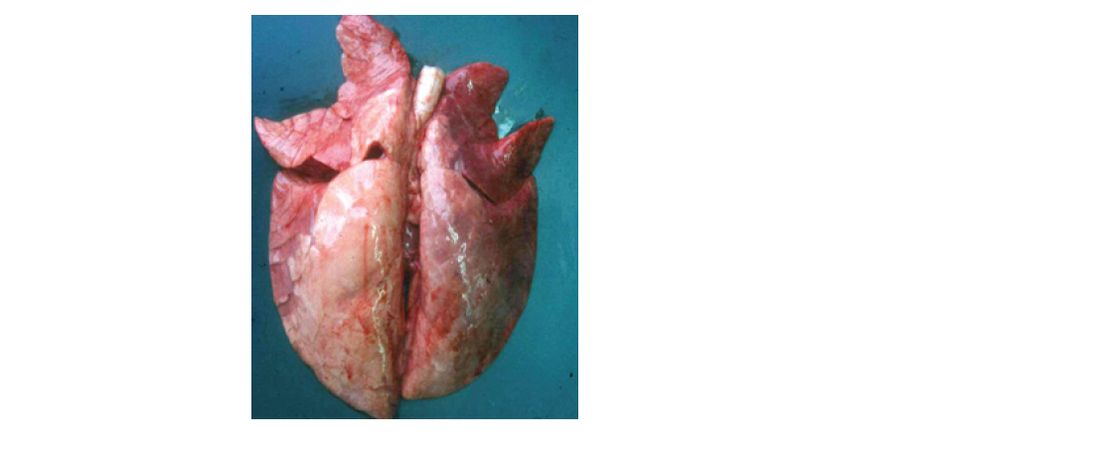

The catarrhal pneumonia leads to consolidation of the lung and is mainly observed in the cranio-ventral lobes when a slaughterhouse check is performed (see Figure 1).

Bacterial isolation is difficult and time-consuming. Hence, other diagnostic techniques such as PCR tests (lung tissue, swabs or bronchio-alveolar lavages), serology, histopathology, immunohistochemistry and immunofluorescence assays are frequently applied.